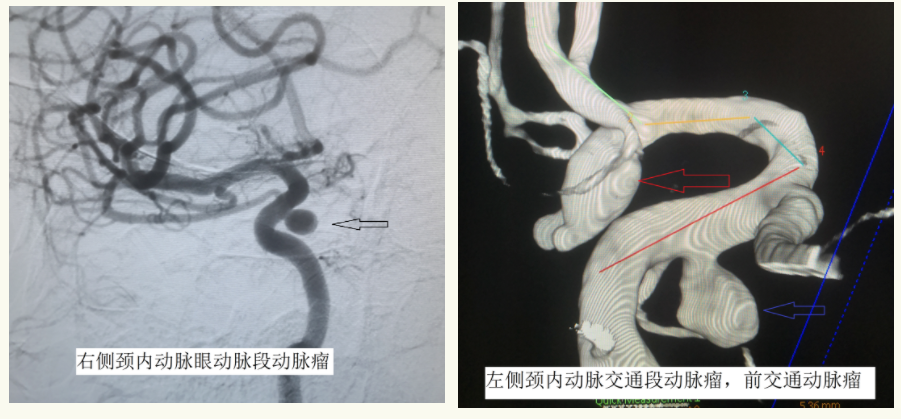

神经外科二组主任王宝庆,副主任医师郭知伟、住院医师王尧在病人病情趋于稳定的情况下迅速为患者做了脑血管造影,明确诊断,找出病因。DSA检查结果显示:颅内多发动脉瘤(右侧颈内动脉眼动脉段动脉瘤,左侧颈内动脉交通段动脉瘤,前交通动脉瘤。其中前交通动脉瘤形态不规则,呈现分叶状有小埠,且与头部CT显示血肿位置一致。前交通动脉瘤破裂出血是本次发病的罪魁祸首。)

术中工作角度造影:证实动脉瘤栓塞满意,载瘤动脉通畅,颅内血管均通畅,血供良好。

手术前后造影对比,前后交通动脉瘤均消失,治疗效果满意。